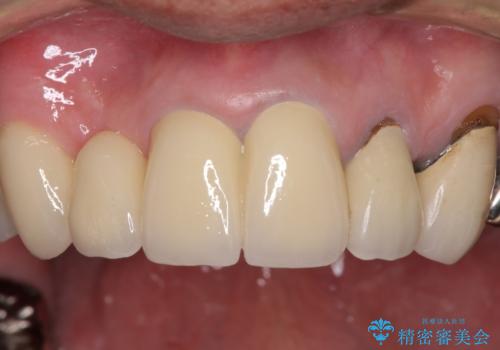

欠けてしまった前歯のブリッジをオールセラミックブリッジへ

- 前歯のブリッジのセラミックが欠けてしまい、作り直したいとのことで来院された患者様です。

犬歯はブリッジの中で虫歯が進行していたため、根管治療からやり直しをした後、オールセラミックブリッジにて補綴することとしました。

歯肉が少し退縮していたため、補綴治療のやり直しにより歯が少し長く見えるようになりましたが、自然な口元に仕上がり、患者様には大変満足していただきました。